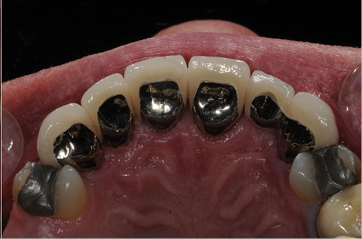

These are full crowns. Before shows old failing amalgam restorations.